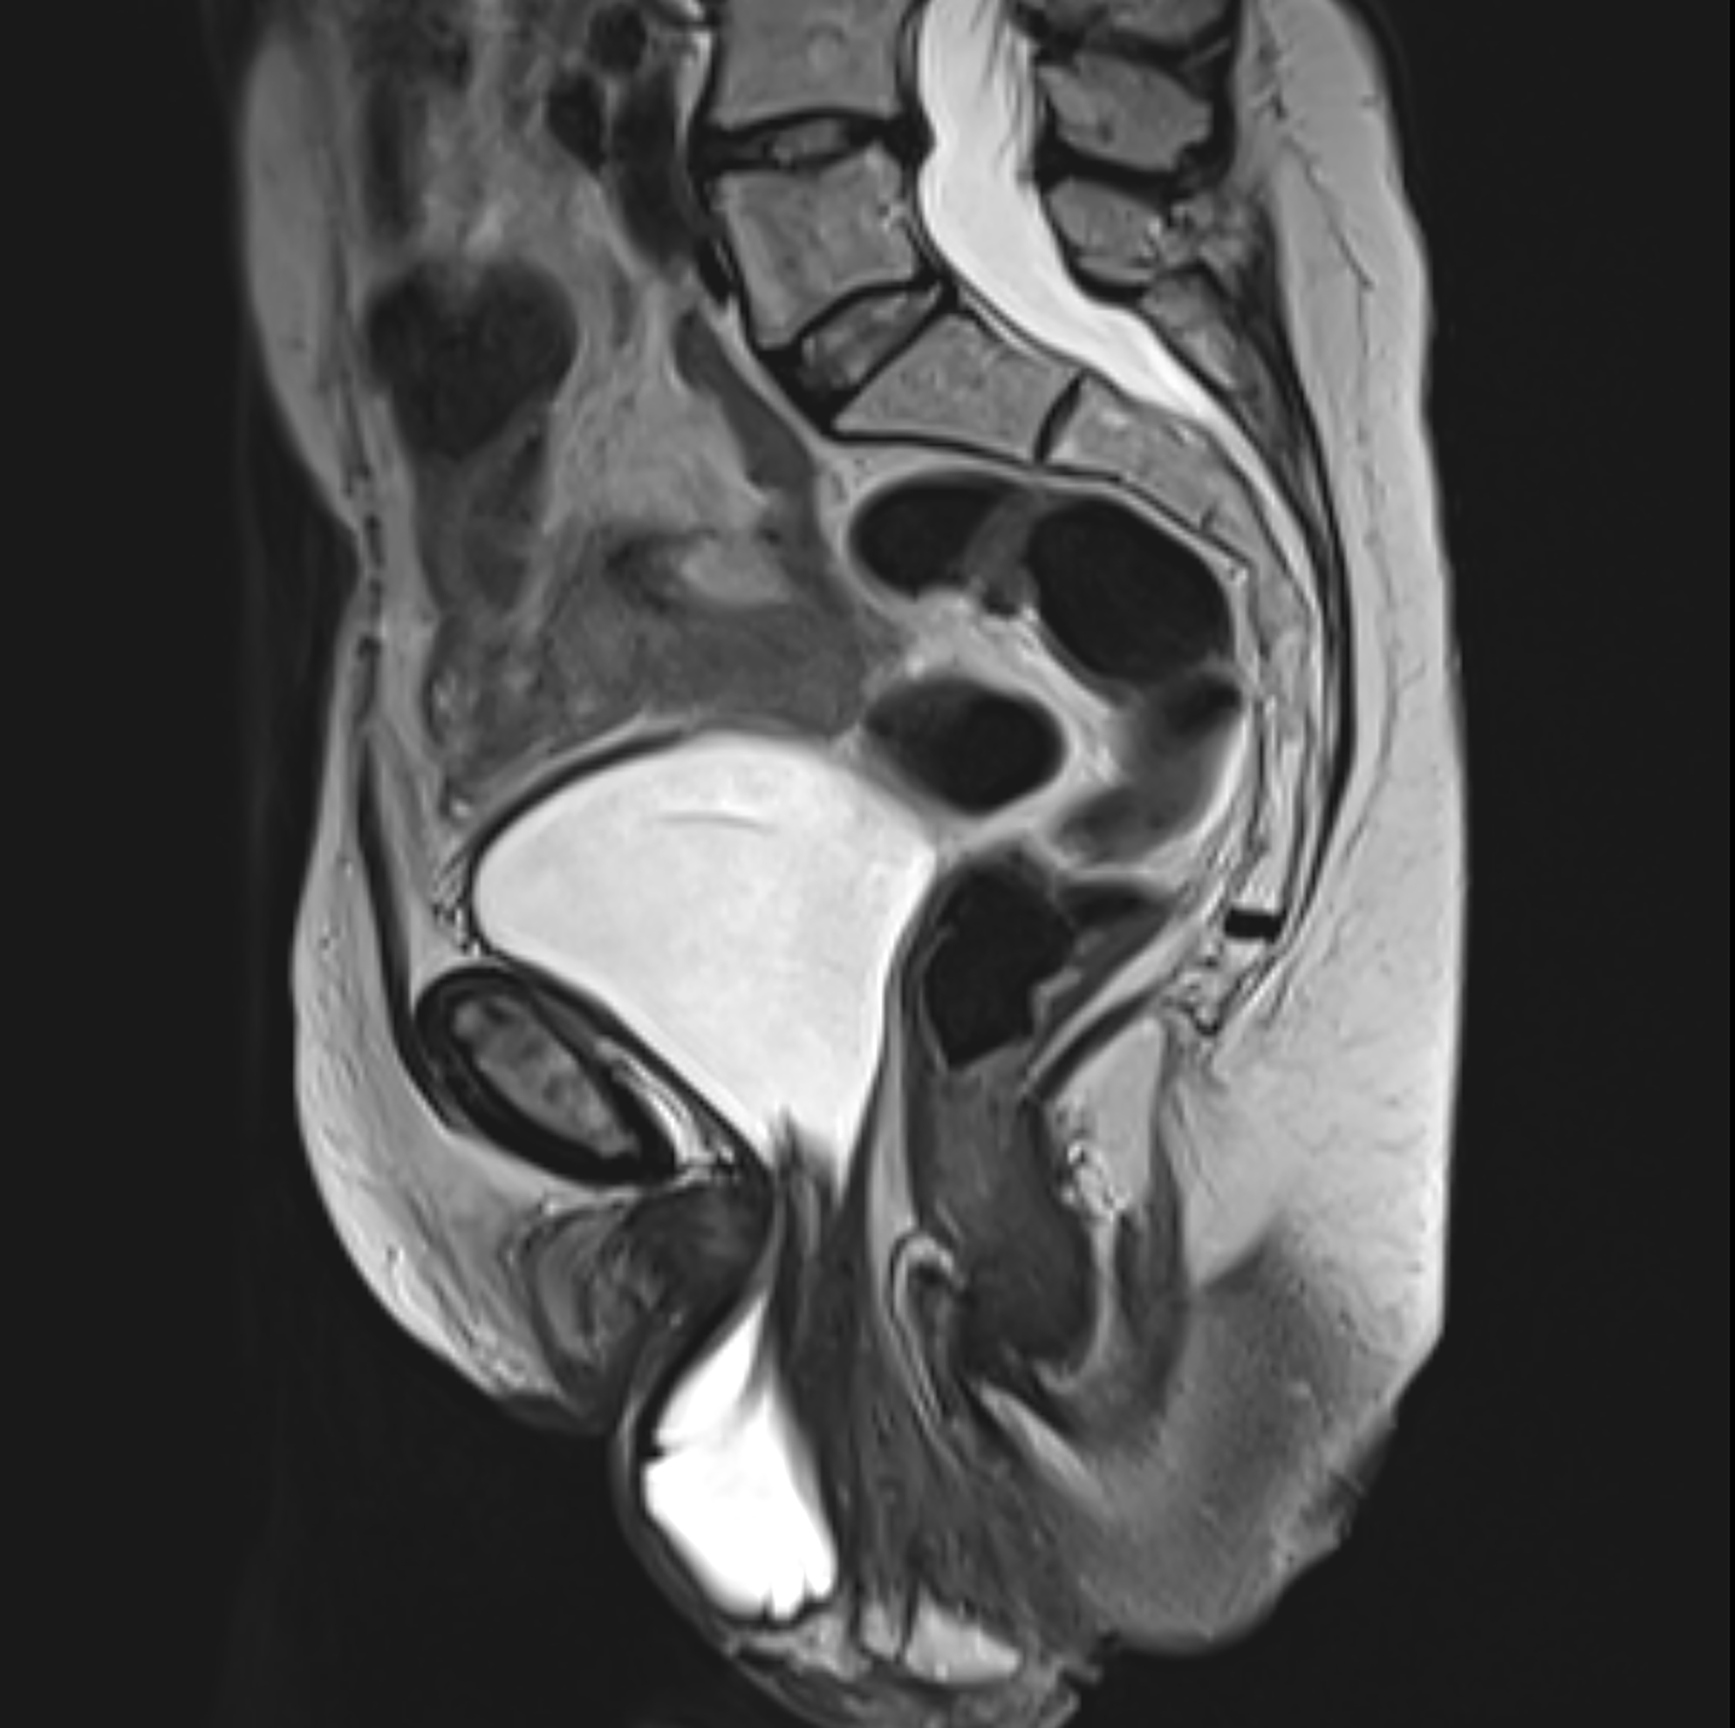

Treating Uterine Prolapse without Surgery The PFPT Approach

Treating Uterine Prolapse without Surgery The PFPT Approach How To Fix Bladder Prolapse Without Surgery Prolapse results when the pelvic floor tissues are overstretched and weakened, just like overstretching a spring. Pelvic organ prolapse can be treated and improve without surgery in some women. Your pelvic floor muscles should work to help support your pelvic organs (i.e. Most cases that are mild can be treated without surgery, and most severe prolapsed bladders can be. Anterior. How To Fix Bladder Prolapse Without Surgery.